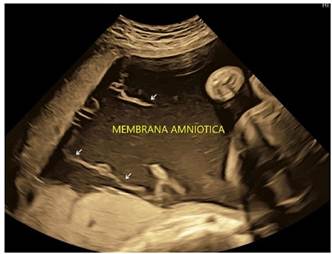

Durante la cesárea se presentó atonía uterina, misma que no respondió a uterotónicos procediéndose a realizar histerectomía subtotal con conservación de anexos, el diagnostico final de Histopatología, reportó Útero de Couvelaire. El departamento de Cirugía Neonatal realizó como primera medida, el mismo día del nacimiento, liberación de membrana amniótica parcial (Figura 5) y en un segundo tiempo se procedió a realizar liberación completa del anillo constrictor, con evolución satisfactoria (Figura 6). El examen realizado a los cinco años muestra una completa recuperación del miembro funcional y estética del miembro (Figura 7). En el seguimiento trabajaron Médicos de las sub especialidades de Embarazo de alto riego Obstétrico, Medicina Fetal, Terapia Neonatal Cirujanos Pediatras, etc. Que dependen del Servicio de Ginecología y Obstetricia.

No existe un patrón específico en el estudio de imágenes para identificar una ruptura de membranas amnióticas; ecográficamente se puede observar imágenes lineales libres que nadan en el líquido amniótico y pueden estar unidos, o no, al feto (Figura 8). Frente a este hallazgo se debe realizar un estudio anatómico fetal buscando anomalías estructurales y anillos de constricción, principalmente en los miembros, con elefantiasis distal o amputaciones distales. Se debe hacer diagnóstico diferencial con otras anomalías como sinequias uterinas, tabique Mulleriano.